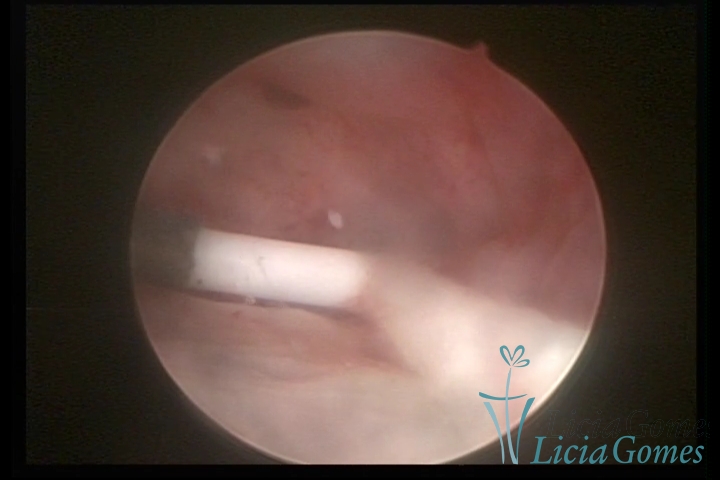

Canal cervical com fio do DIU